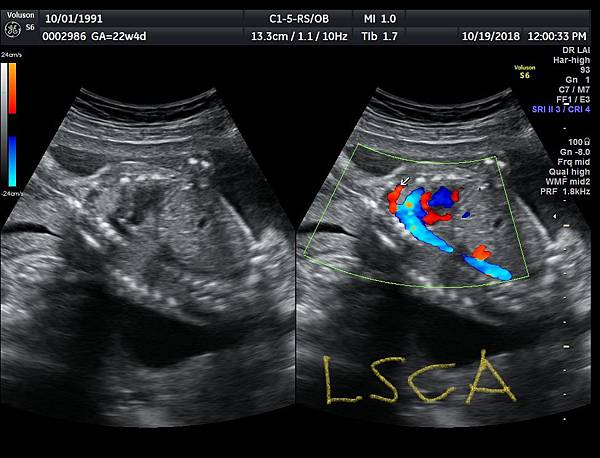

孕兒診所備忘錄 384 aorta 3 branches images from longitudinal view

aorta 3 branches images from longitudinal view